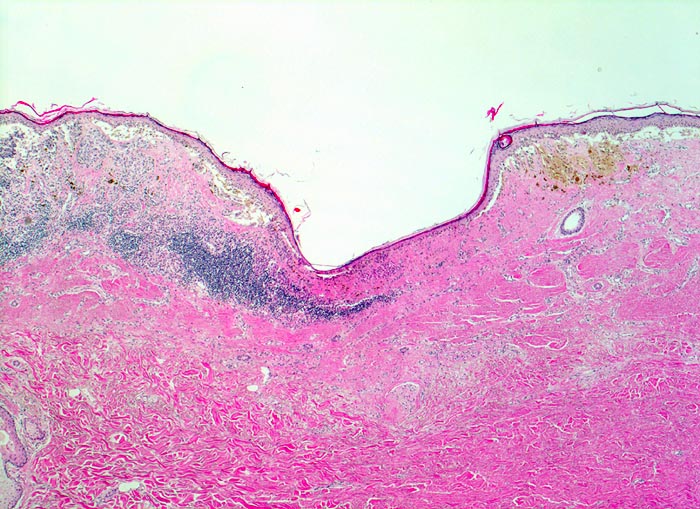

AP/ Malignes Melanom vom superfiziell spreitenden Typ

Malignes Melanom vom superfiziell spreitenden Typ

• Stark asymmetrischer, unregelmässig pigmentierter dermoepidermaler melanozytärer Tumor.

• Wechselnd Akanthose und Atrophie (Consumption) der Epidermis mit langstreckiger Ulzeration des Epithels im Bereich der grössten Tumordicke.

• Die epidermale Melanomkomponente besteht aus in der Epidermis aufsteigenden atypischen Melanozyten (=pagetoide Ausbreitung) und unterschiedlich grossen Zellnestern durchmischt mit Melanophagen.

• Epidermale Komponente breiter als dermale Komponente (SSM)

• Verschieden grosse, teils konfluierende (Sheets) Tumorzellnester in der Dermis.

• Fehlende Ausreifung zur Tiefe hin (keine Abnahme der Zellgrösse, der Grösse der Zellnester oder der Pigmentierung zur Tiefe).

• Tumorinfiltration der retikulären Dermis (Clark Level IV)

• Wichtige Malignitätskriterien bei melanozytären Tumoren: Kombination von schweren zytologischen Atypien und zahlreichen Mitosen in dermalen Tumorzellen.

• Epitheloide rund-ovale Tumorzellen mit reichlich Zytoplasma mit unterschiedlich starker Pigmentierung der unterschiedlichen Tumorzellklone. Grosse hyperchromatische Zellkerne mit einem oder mehreren prominenten eosinophilen Nukleolen.

• Fokale Ansammlungen von stark pigmentierten Melanophagen in der dermalen Tumorkomponente.

• Unregelmässig verteiltes dermales tumorinfiltrierendes lymphoplasmazelluläres Entzündungsinfiltrat.

• Links auf dem Präparat sind unterhalb des Melanoms dermale Reste eines vorbestehenden gewöhnlichen Naevuszellnaevus erkennbar. Naevuszellen deutlich kleiner und zytoplasmaärmer mit kaum erkennbaren Nukleolen.

• Solare Elastose (chronische UV-Schädigung).